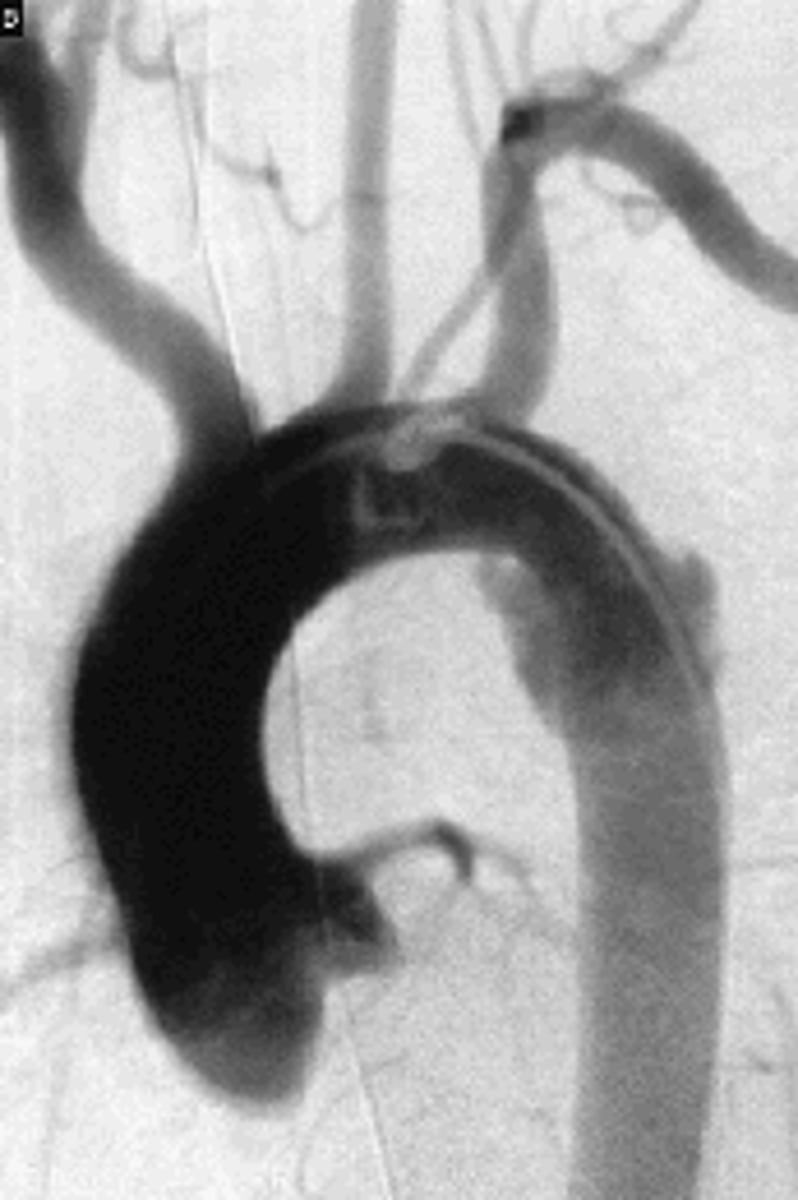

Angiocardiography

radiography of the heart and great vessels after intravenous injection of a radiopaque solution

Aortography

radiography of the aorta

Aortagram

record produced from a aortography